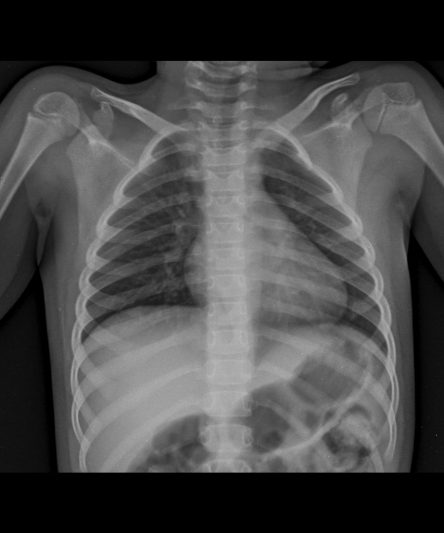

Microskan with Ultra high frequency can take the Lateral Lumbar Spine image of a 90 kg Patient with the correct image receptor